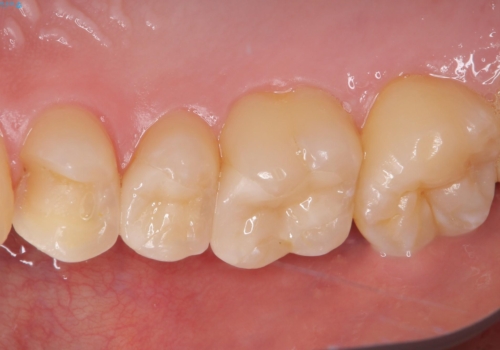

詰め物が外れた セラミックインレー修復

- 以前治療した詰め物が外れてしまい、冷たいものがしみることを主訴として来院された患者様です。

むし歯がないことを確認し、セラミックインレーにて修復するととしました。

適合の良いセラミックインレーの装着により、冷たいものがしみる症状はなくなりました。